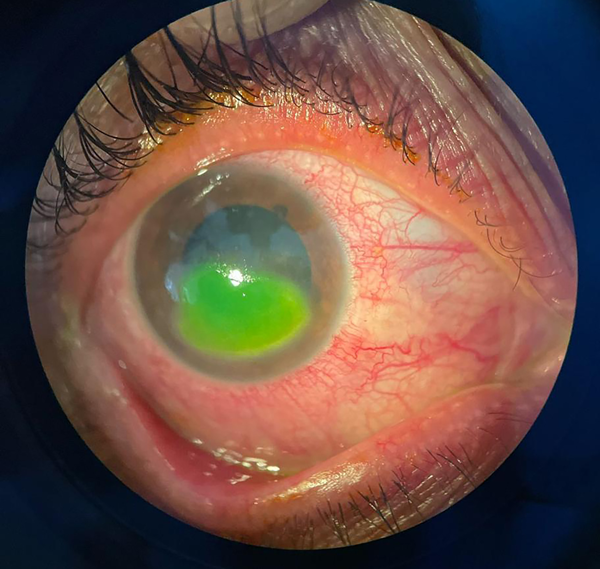

Al examinarla, su agudeza visual sin corrección (AVSC) en ojo derecho (OD) era de cuenta dedos a 3 metros y en ojo izquierdo (OI) de 7/10, y su agudeza visual mejor corregida de 1/10 y 9/10 en OD y OI respectivamente. A la biomicroscopía del OD se observó defecto epitelial amplio (fig. 1), leucoma central con adelgazamiento estromal marcado, signos de queratopatía tóxica severa y signos sugestivos de microperforación. El fondo de ojo resultaba inaccesible en ese momento por la opacidad de medios, mientras que el OI se encontró dentro de los parámetros normales.

Figura 1. Epiteliopatía observada en la primera consulta.